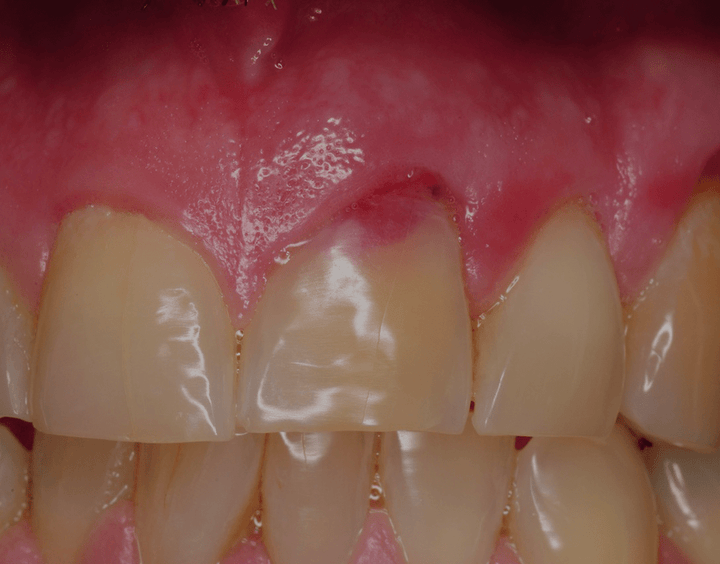

Dental Resorption Symptoms . Learn about its causes, symptoms, and treatment options for better oral. What causes adult root resorption? Root resorption symptoms can come in the form of pain, swelling, and loosening of your teeth. Err affects the surface of the root and is a common sequel to dental luxation and avulsion injuries. Err can advance rapidly, such that an. However, most cases are asymptomatic. red, swollen, or inflamed gums. In some cases, the patient may. Tooth resorption is when the tooth structure is damaged or destroyed. Symptoms from tooth resorption can include pain, redness and swelling. There are different ways to manage tooth resorption, but it’s best to prevent it in the first place. When it comes to root resorption, there is no clear set of symptoms. When it comes to tooth or root resorption, there is no clear set of symptoms. Holes in teeth that aren’t cavities. In some cases, the patient may not notice the problem for years.

Holes in teeth that aren’t cavities. Tooth resorption is when the tooth structure is damaged or destroyed. When it comes to tooth or root resorption, there is no clear set of symptoms. Common signs of external resorption include: However, most cases are asymptomatic. red, swollen, or inflamed gums. In some cases, the patient may not notice the problem for years. What causes adult root resorption? Internal resorption in teeth can lead to serious dental issues. Err can advance rapidly, such that an.

Dental Resorption Symptoms Holes in teeth that aren’t cavities. Err can advance rapidly, such that an. There are different ways to manage tooth resorption, but it’s best to prevent it in the first place. red, swollen, or inflamed gums. Learn about its causes, symptoms, and treatment options for better oral. In some cases, the patient may. Holes in teeth that aren’t cavities. Internal resorption in teeth can lead to serious dental issues. Common signs of external resorption include: Symptoms from tooth resorption can include pain, redness and swelling. What causes adult root resorption? In some cases, the patient may not notice the problem for years. When it comes to root resorption, there is no clear set of symptoms. Err affects the surface of the root and is a common sequel to dental luxation and avulsion injuries. Tooth resorption is when the tooth structure is damaged or destroyed. When it comes to tooth or root resorption, there is no clear set of symptoms.